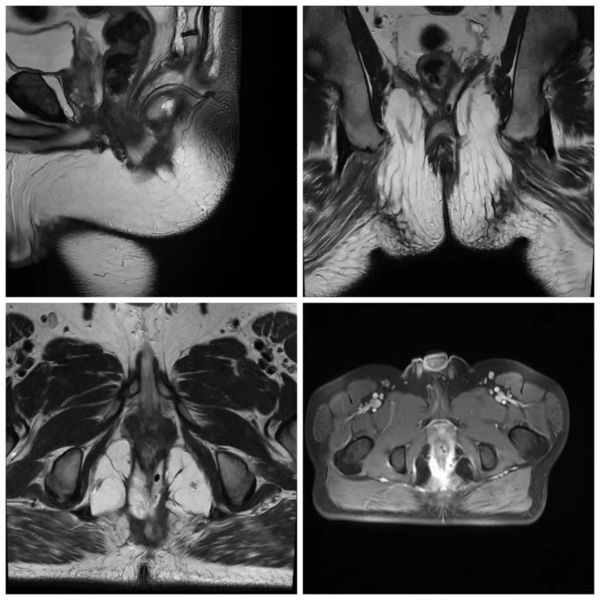

2022年4月11日,患者再次于我院复查,肛管MRI可见瘘管范围明显缩小,科主任王定树认为第三期根治性手术时机已成熟。术中,手术团队沿原切口进入,超声刀切断后方肛门内外括约肌及4/5肛直环,清除肌间残留病灶,并切开后方直肠壁至破损处行直肠推移瓣手术,切口内放置引流管引流,第三期手术顺利完成。经过术后2个月恢复,患者大便已能基本完全控制,伤口也大部分愈合,基本康复。

第三期手术前肛管MRI图 “当肛瘘的瘘管穿过超过30%的肛门外括约肌、瘘管呈马蹄形、女性患者的前位瘘管、多条瘘管、复发瘘管或存在失禁时,可被定义为复杂性肛瘘。”普四科主任王定树介绍道:肛瘘治疗的目标是根除瘘管,防止复发,减少术后感染并发症,以及对肛门自制力最低限度的影响,术前M R I精准评估、术中精细操作、术后精心护理是手术成功的三大要素。

第三期手术前肛管MRI图